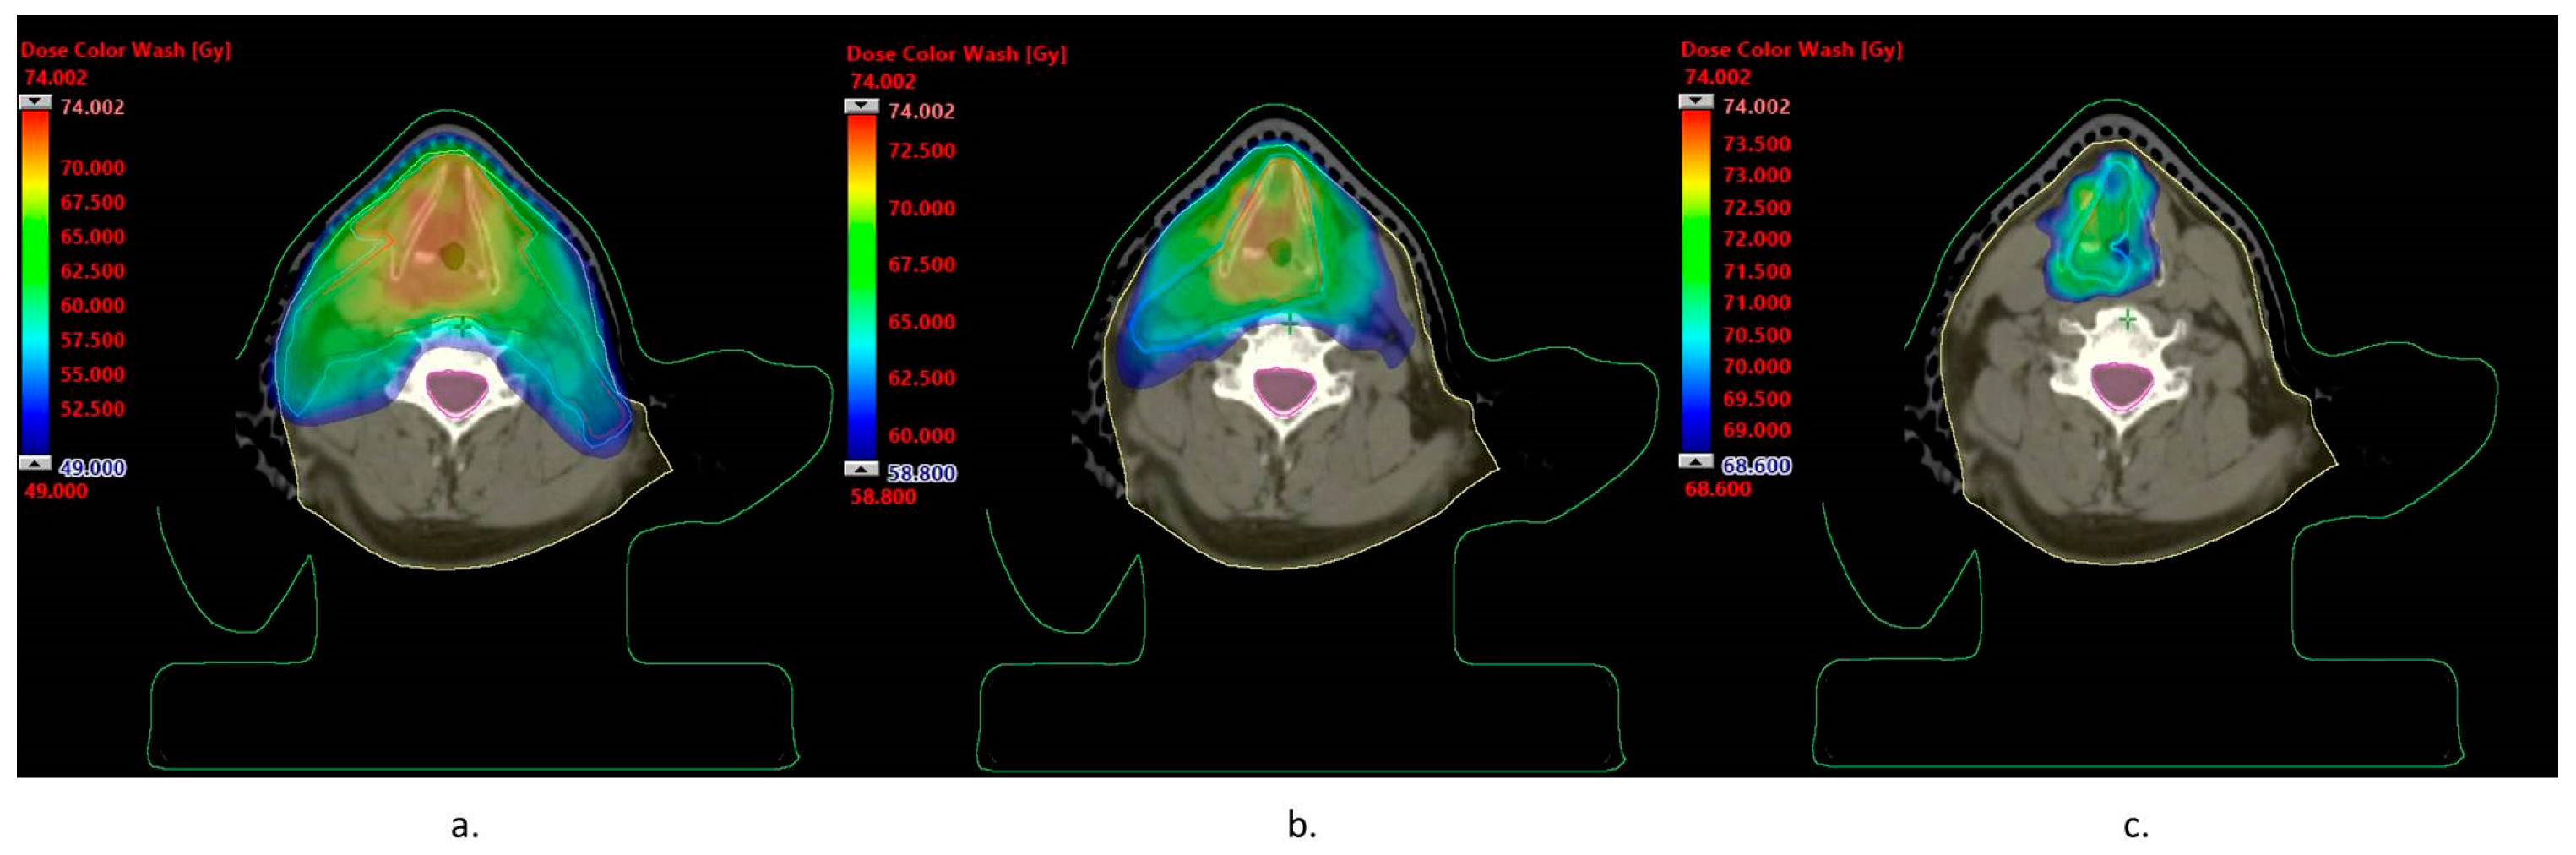

| Dmin [Gy] | Dmax [Gy] | Dmean [Gy] | |

|---|---|---|---|

| CTV 50 | 48.8 | 74.0 | 61.5 |

| PTV 50 | 41.7 | 74.0 | 60.3 |

| CTV 60 | 59.5 | 74.0 | 68.5 |

| PTV 60 | 57.9 | 74.0 | 67.9 |

| CTV 70 | 69.0 | 74.0 | 71.2 |

| PTV 70 | 68.6 | 74.0 | 71.2 |

| Spinal canal | 0.0 | 44.8 | 17.8 |

| Brainstem | 1.0 | 20.8 | 3.0 |

| Brain | 0.4 | 11.7 | 1.4 |

| Parotid gland left | 4.9 | 57.7 | 25.1 |

| Parotid gland right | 4.2 | 64.0 | 26.5 |

| Cochlea left | 2.3 | 4.6 | 3.3 |

| Cochlea right | 2.2 | 3.4 | 2.7 |

| Eye left | 0.7 | 2.3 | 1.3 |

| Eye right | 0.7 | 1.8 | 1.1 |

| Lens left | 0.9 | 1.3 | 1.1 |

| Lens right | 0.8 | 1.1 | 1.0 |

| Chiasm | 1.5 | 1.9 | 1.6 |

| Mandible | 2.8 | 70.9 | 30.7 |

| Thyroid | 40.3 | 56.0 | 46.7 |

| Lung left | 0.0 | 47.7 | 1.7 |

| Lung right | 0.0 | 48.4 | 2.0 |

| Vessels left | 48.9 | 67.6 | 59.2 |

| Vessels right | 48.9 | 72.6 | 63.2 |